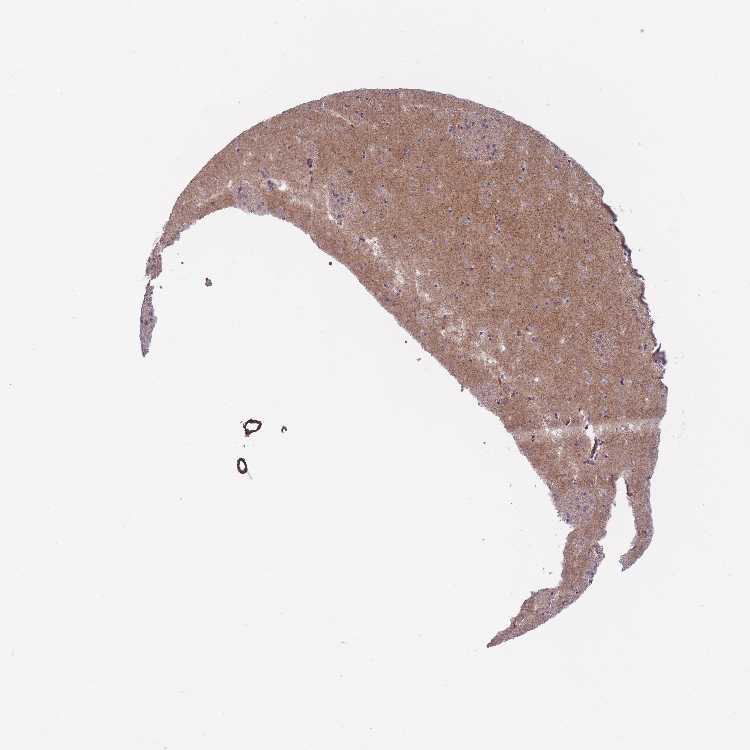

CAUDATE - Antibody stainingi

Antibody staining in the annotated cell types in the current human tissue is reported as not detected, low, medium, or high, based on conventional immunohistochemistry profiling in selected tissues. This score is based on the combination of the staining intensity and fraction of stained cells.

Each image is clickable and will lead to virtual microscopy that enables deeper exploration of all samples and also displays staining intensity scores, fraction scores and subcellular localization as well as patient and tissue information for each sample.

Antibody HPA042708Antibody HPA043505

Glial cells LowNot detected

Neuronal cells HighLow